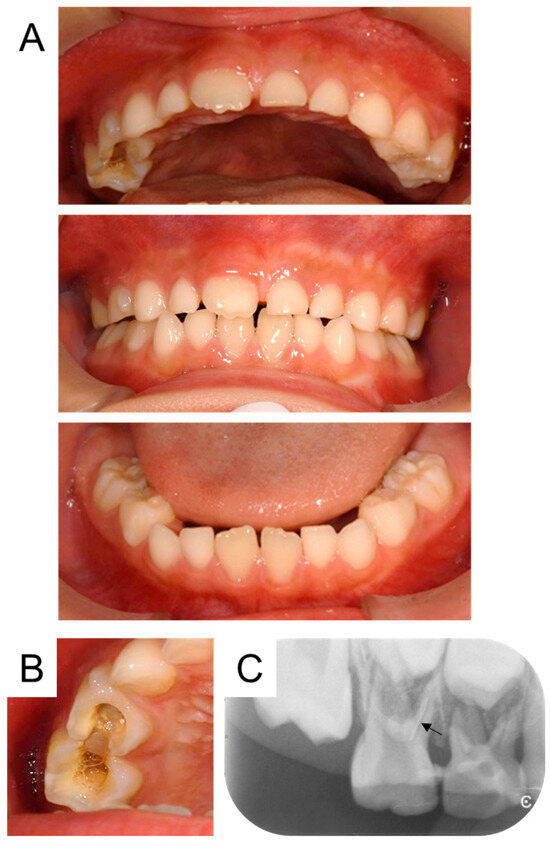

2. Detailed Case Description

| Present case | #55 | Mesio-buccal canal | Reamer | 17 months | Enamel hypoplasia |